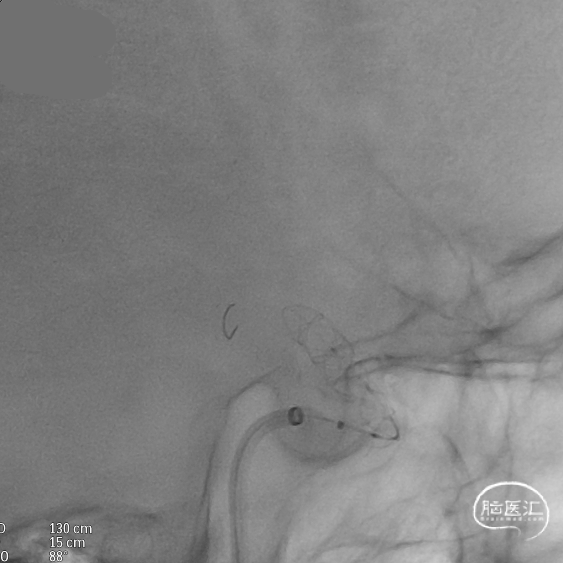

微导管到位:Synchro微导丝引领支架微导管通过病变血管进入大脑中动脉M1段远端。

支架到位,远端打开(正侧位):4.75-20mm支架在大脑中动脉M1段打开,回撤至C6段远端锚定。支架释放过程中,轻柔推送支架系统,可见支架导管沿血管壁大弯侧走行,支架打开良好。